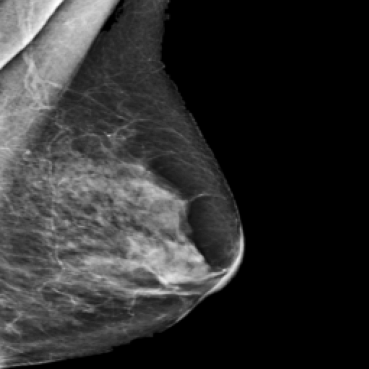

The 136 true outliers are classified into seven categories by the professional radiologist: implant, pacemaker, cardiac loop recorder, improper radiography, atypical lesion/calcification, incorrect exposure parameter and improper placement. It is worth noting that, despite the fact that mammograms with implants were eliminated during the preprocessing step (see Section 2.6), there were still mammograms with implants remaining since they were incorrectly categorised as having no implants. Figure 1 depicts representative outliers for each category, and Table. 4 displays the number and percentage of outliers in each category given that that the total number of true outliers is 136.

Figure 1: Examples of true outlier subgroups in the ADMANI dataset. From left to right and top to bottom, the outlier types are: implant, pacemaker, cardiac loop recorder, improper radiography, improper radiography, atypical lesions/calcification, incorrect exposure parameter, improper placement. Improper radiography is classified into two subtypes: those with heterogeneous pectoral muscle and the rest, respectively.